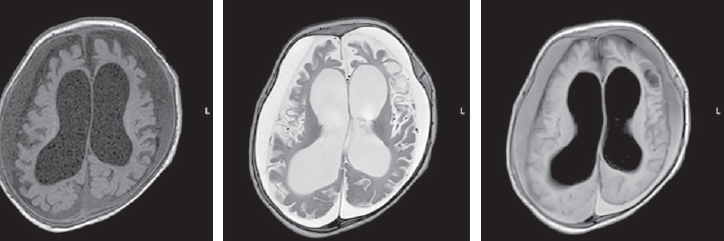

The child’s condition remained critical, with impaired consciousness, extension contractures in the elbow and knee joints, and non-epileptic paroxysmal states, such as bronchospasm and apnea persisting. Startle reflexes were pronounced and with any tactile stimulation, startle (generalized myoclonus) was registered. With the progression of neurological disorders, an increase in the cystic-atrophic changes was noted and hydrocephalus was formed. The data of MRI over a time, performed at the age of four months, are presented in Fig. 3.

Fig. 3. Magnetic resonance imaging of a patient at the age of 4 months. Axial sections, T1 VI, T2 VI, Flair. There is a negative dynamics in the form of cystic-atrophic changes in the large hemispheres of the brain with the formation of atrophic hydrocephalus. The appearance of symmetrical subshell clusters in the form of subdural hygromas

Рис. 3. Магнитно-резонансная томограмма пациента в возрасте 4 мес. Аксиальные срезы, Т1ВИ, Т2 ВИ, Flair. Наблюдается отрицательная динамика в виде кистозно-атрофических изменений в больших полушариях головного мозга с формированием атрофической гидроцефалии. Появление симметричных подоболочечных скоплений в виде субдуральных гигром